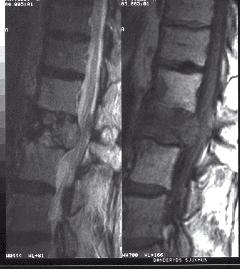

På onsdagsmorgonen gick Yngvar Krukhaug, Bergen, på ett didaktiskt sätt igenom eviden sen för olika behandlingsstrategier av distala radiusfrakturer. ”Take home message” blev att de data vi grundar våra beslut på generellt är av undermålig kvalité, att gipsbehandling kan användas i 80 % av fallen och att det nu finns evidens för användning av volar plattfixation vid instabila AO C1 och C2 frakturer. Vid mer splittrade frakturer finns inga data som visar att volar platta är bättre än externfixation, nå got som ytterligare diskuterades vid efterföl jande symposium om indikationer för vinkel stabila plattor med Ingvar Allvin, Örebro, som moderator.